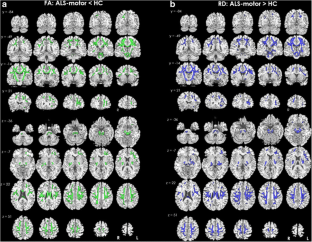

The phenotypic heterogeneity in amyotrophic lateral sclerosis (ALS) implies that patients show structural changes within but also beyond the motor cortex and corticospinal tract and furthermore outside the frontal lobes, even if frank dementia is not detected. The aim of the present study was to investigate both gray matter (GM) and white matter (WM) changes in non-demented amyotrophic lateral sclerosis (ALS) patients with or without cognitive impairment (ALS-motor and ALS-plus, respectively). Nineteen ALS-motor, 31 ALS-plus and 25 healthy controls (HC) underwent 3D–T1-weighted and 30-directional diffusion-weighted imaging on a 3 T MRI scanner. Voxel-based morphometry and tract-based spatial-statistics analysis were performed to examine GM volume (GMV) changes and WM differences in fractional anisotropy (FA), axial and radial diffusivity (AD, RD, respectively). Compared to HC, ALS-motor patients showed decreased GMV in frontal and cerebellar areas and increased GMV in right supplementary motor area, while ALS-plus patients showed diffuse GMV reduction in primary motor cortex bilaterally, frontotemporal areas, cerebellum and basal ganglia. ALS-motor patients had increased GMV in left precuneus compared to ALS-plus patients. We also found decreased FA and increased RD in the corticospinal tract bilaterally, the corpus callosum and extra-motor tracts in ALS-motor patients, and decreased FA and increased AD and RD in motor and several WM tracts in ALS-plus patients, compared to HC. Multimodal neuroimaging confirms motor and extra-motor GM and WM abnormalities in non-demented cognitively-impaired ALS patients (ALS-plus) and identifies early extra-motor brain pathology in ALS patients without cognitive impairment (ALS-motor).